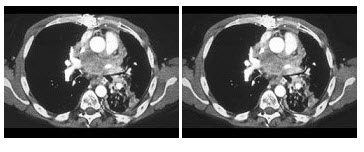

7、单项选择题

根据所提供的图像,该病灶最好的分期为()

A.Bosniak1

B.Bosniak2

C.Bosniak3

D.Bosniak4

E.以上都不是